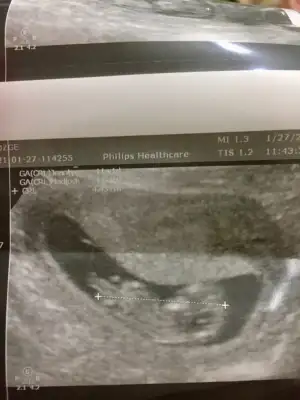

dr soylemeden siz gorun genital nub teorisi ( bebegin cinsiyeti)

13. Haftada kız demiştin canım doktorum da başından beri öyle diyor bugün de öyle dedi. Cikintiyi çizebilir misin 😍

Canım emin değilim en iyi 11 12 13 haftalar olmalı dedim yinede USG ile uğraşıp cizeyim gördüğüm nub ise 🙈

Bu nub değil artık çizdigim organı oluşmuş oluyor yanılmış olabilirim bu haftalar benim alanım degil 🙈 gördüğüm pipi olmayabilir ☺️Eki Görüntüle 2770911

Kız tabiki burda ama sonraki büyük haftada nub olmaz ☺️ demekki kordon gelmiş yoksa diğeri net bariz kız nubu 🙈